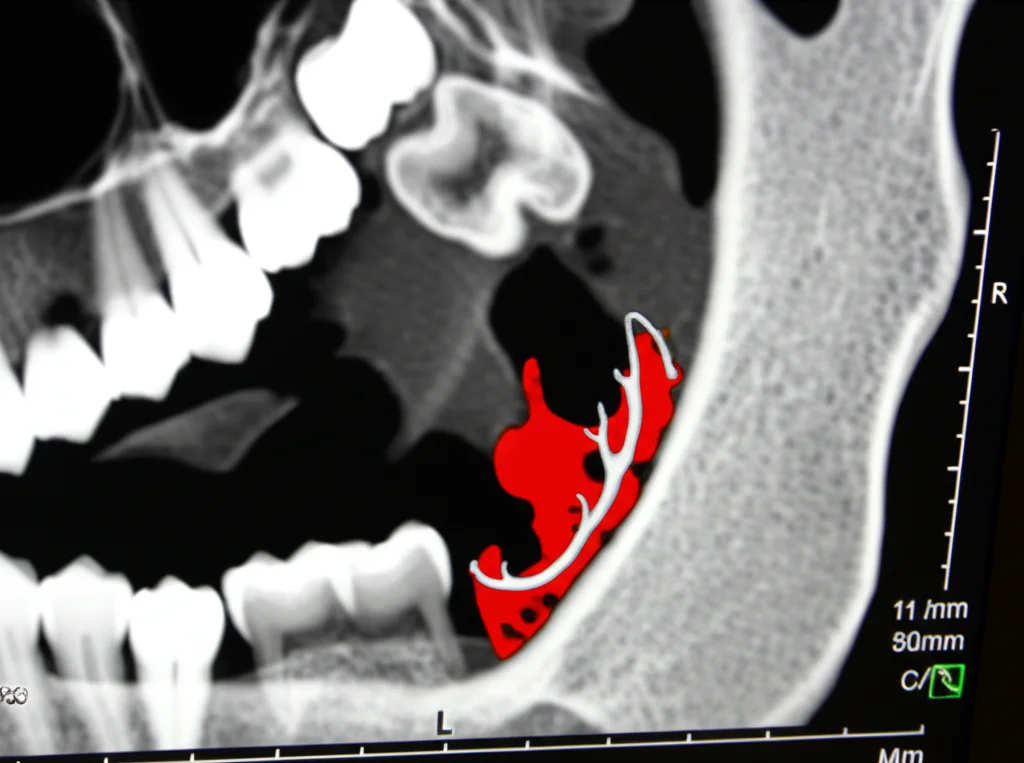

Ecco perché oggi abbiamo un alleato potentissimo: la Cone-Beam Computed Tomography (CBCT). Questa tecnologia è una vera rivoluzione! Ci fornisce immagini tridimensionali (3D) ad alta risoluzione dell’intera regione maxillo-facciale, con una dose di radiazioni nettamente inferiore rispetto alla TC tradizionale (MSCT). La CBCT è incredibilmente accurata e affidabile per le misurazioni lineari, permettendoci di vedere esattamente:

- La profondità della fossa sottomandibolare

- La sua forma e le sue variazioni

- Il percorso preciso del canale mandibolare

- La relazione spaziale tra queste due strutture

- Posizione del Canale Mandibolare: Qui arriva un dato cruciale. Nella maggior parte dei casi, il canale mandibolare si trovava in posizione inferiore rispetto al punto più profondo della fossa. Tuttavia, sono state osservate anche posizioni parallele e superiori.

- Relazione Profondità-Posizione Canale: È stata trovata una relazione interessante. La profondità media della fossa era minore quando il canale era in posizione parallela, e maggiore quando era in posizione superiore. Questo è importantissimo: anche se una panoramica mostra il canale mandibolare vicino al bordo inferiore della mandibola (facendo pensare a molto spazio sopra), potrebbe esserci una fossa molto profonda proprio sopra il canale, aumentando il rischio di perforazione se si sceglie un impianto troppo lungo basandosi solo sulla 2D.